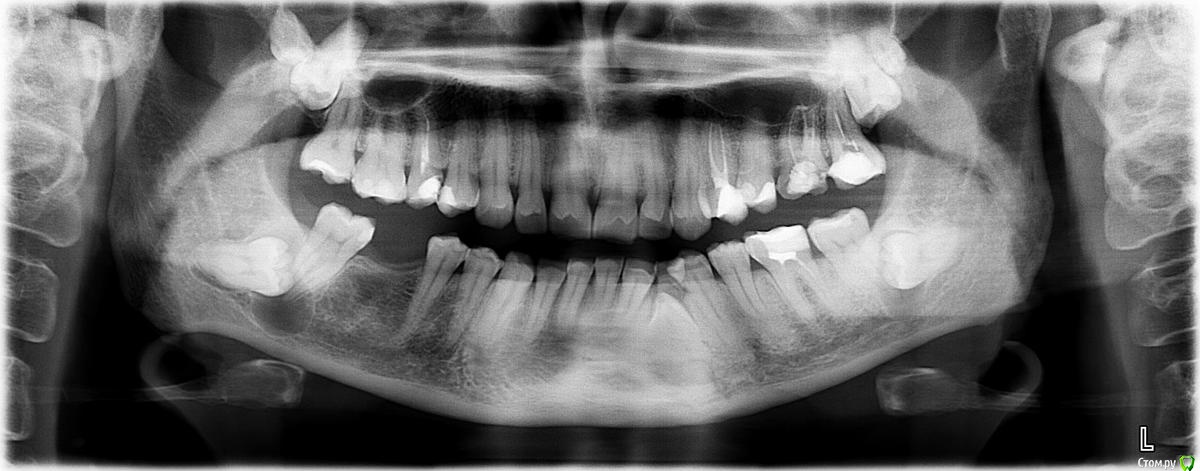

L.E.S.I.K. Опубликовано 16 декабря, 2016 Поделиться Опубликовано 16 декабря, 2016 Пациенкта с 9-ми. Но сегодня удалили только 47 48 и кисту (не сфотографировал) 4 Ссылка на комментарий